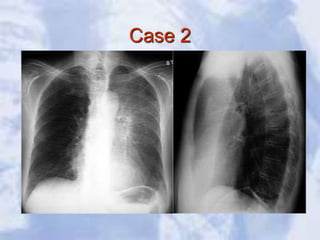

Case 2

LUL Atelectasis: Loss of heart borders/silhouetting. Notice

over inflation on unaffected lung